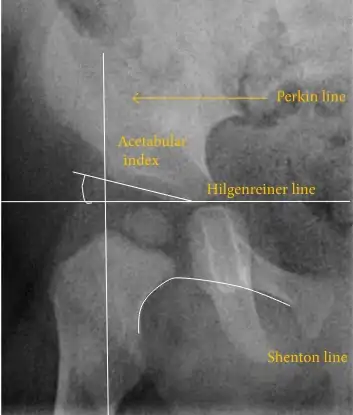

Hip dysplasia diagnosed by ultrasound[40] and projectional radiography ("X-ray").[41] Ultrasound imaging is generally preferred at up to 4 months due to limited ossification of the skeleton.[39][notes 1]

Despite the widespread of ultrasound, pelvis X-ray is still frequently used to diagnose or monitor hip dysplasia or for assessing other congenital conditions or bone tumors.[42] The most useful lines and angles that can be drawn in the pediatric pelvis assessing hip dysplasia are as follows:[42] Different measurements are used in adults.[42]